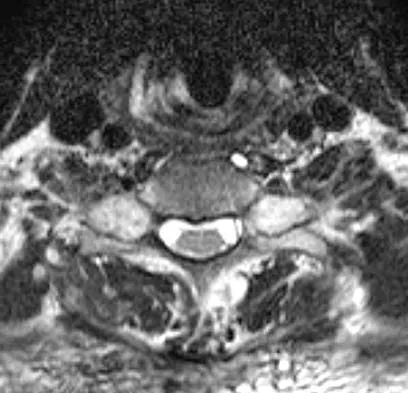

A 65-year-old man with ankylosing spondylitis has neck pain after falling back over his lawnmower, striking his thoracic spine, and forcing his neck into extension. Examination reveals subtle weakness of the intrinsics and finger flexors at approximately 4+/5. Initial management consists of immobilization in a rigid collar, and placing his head in the anatomic position. Radiographs reveal a subtle extension fracture of the lower cervical spine. Approximately 6 hours after the injury, he reports increasing paresthesias in his upper and lower extremities, and examination now shows his intrinsics are 2/5, finger flexors are 3/5, and his triceps are now weak at 4/5 on manual motor testing. In addition, his lower extremities now show weakness in both dorsal and plantar flexion of the ankle in the range of 4/5. Repeat radiographs appear unchanged. An MRI scan is shown in Figure 2. Management should now consist of

Explanation

It is not uncommon for patients with ankylosing spondylitis to sustain extension-type fractures, most typically of the cervicothoracic junction. These fractures can appear nondisplaced or minimally displaced initially, making them difficult to diagnose. Because there is no mobility between vertebrae, fractures tend to occur more like those of a transverse fracture of a long bone. In addition, the vertebral bodies are vascular and their canals are relatively enclosed, making them vulnerable to epidural bleeding. The MRI scan reveals an epidural hematoma located posteriorly on the cord; therefore, the treatment of choice is surgical evacuation and a posterior laminectomy. Because of the intrinsic instability of such fractures at the time of the laminectomy, internal fixation and stabilization with a posterior fusion is warranted. A simple laminectomy will only increase instability, and control is unlikely with halo vest immobilization. An anterior procedure will not effectively treat the problem given the location of the hematoma. Consideration can be given to methylprednisolone and observation; however, this will not eradicate the problem. Bohlman HH: Acute fractures and dislocations of the cervical spine. J Bone Joint Surg Am 1979;61:1119-1142.